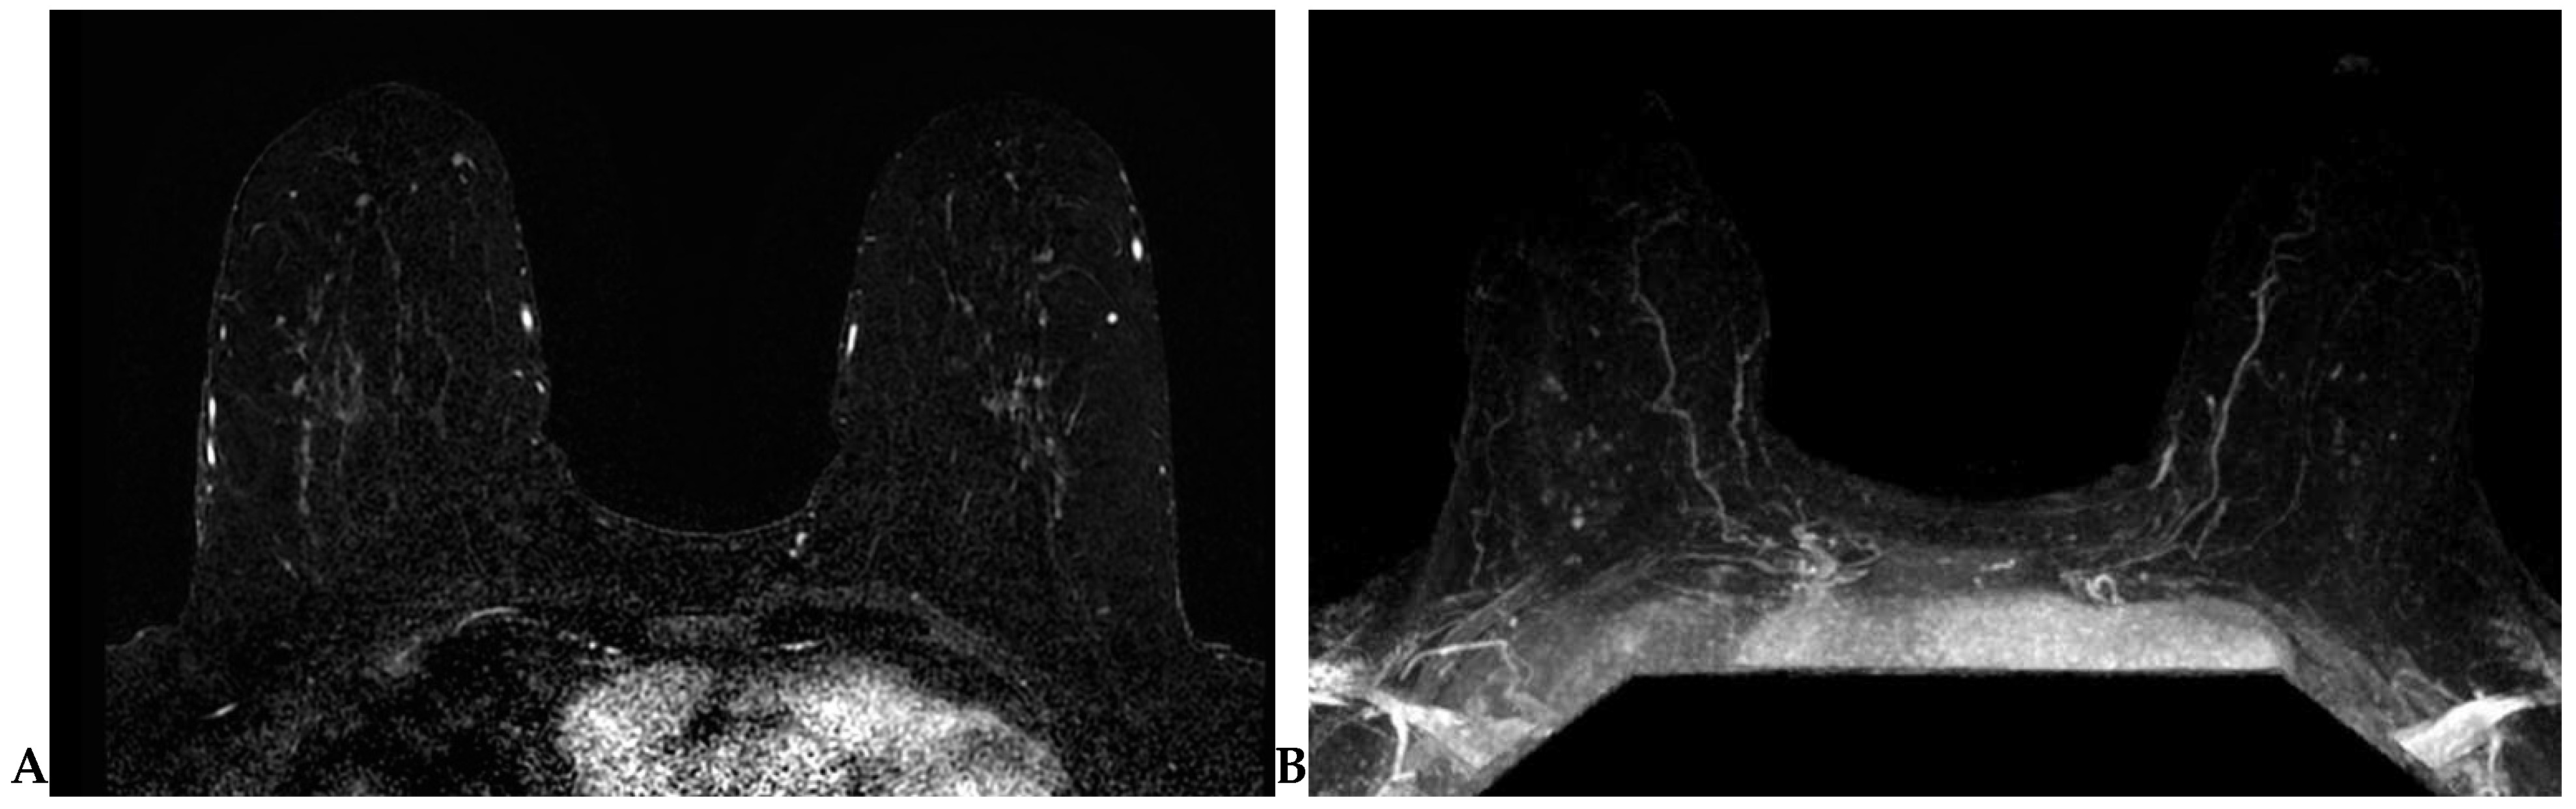

2.4.4. Background Parenchymal Enhancement (BPE)